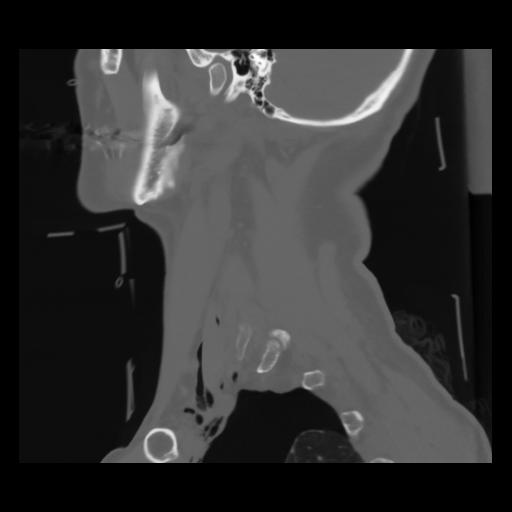

14 P.BLANDAS,,Sagittal,2.000,P.BLANDAS,Sagittal,